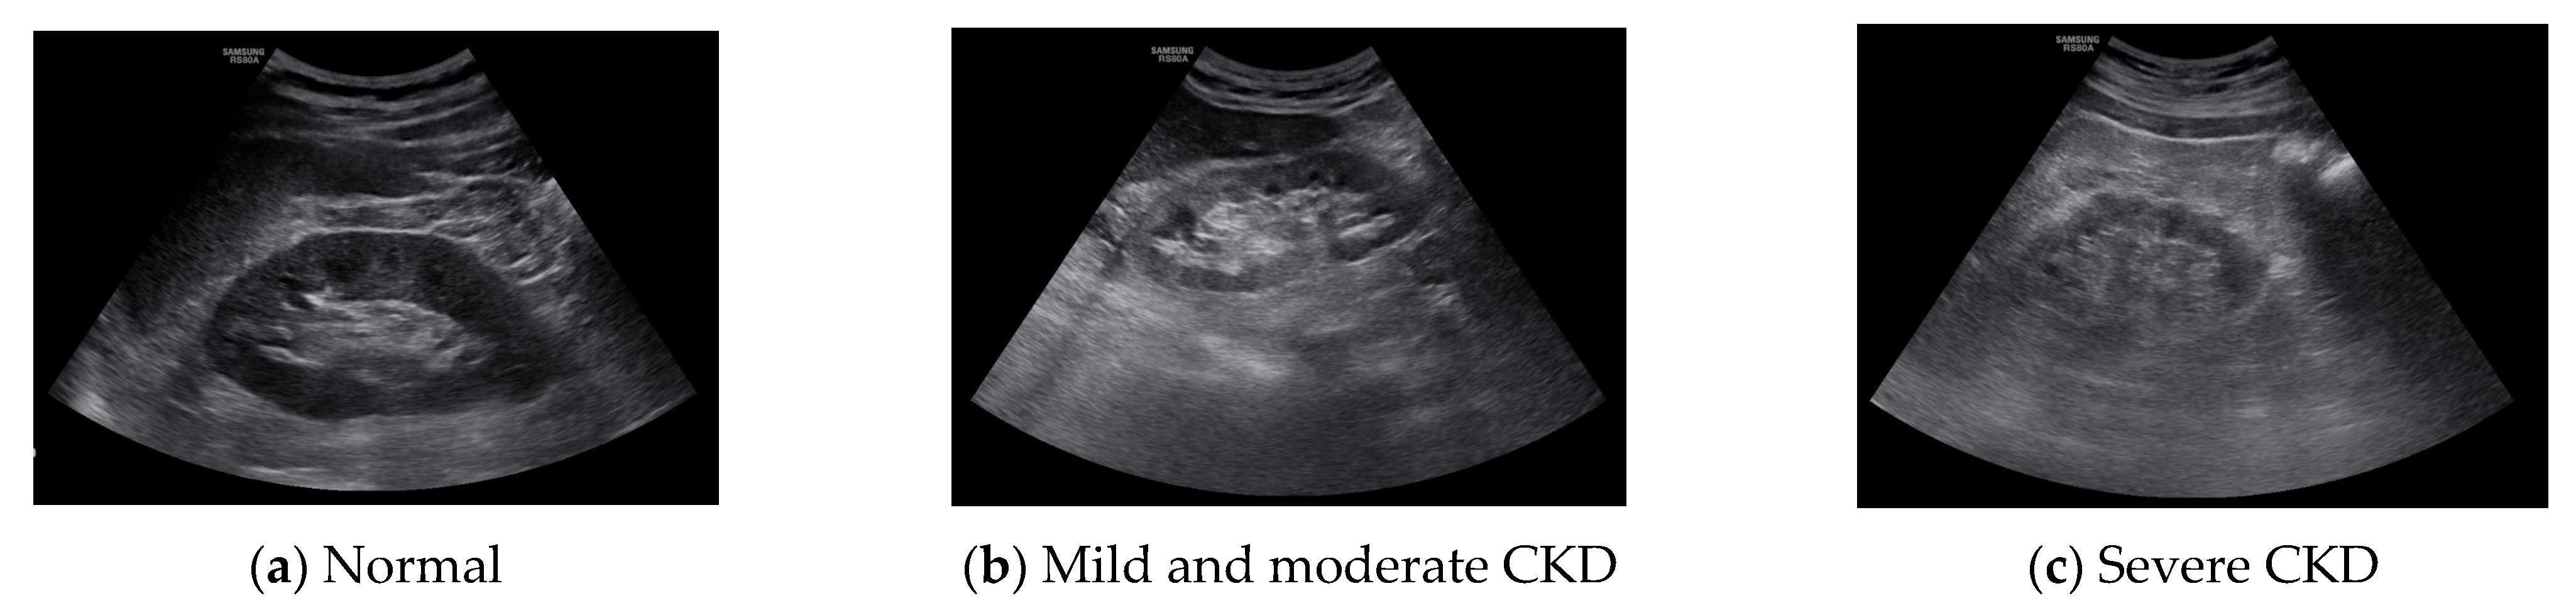

2.2. Experimental Method

The region of interest (ROI) was set in the ultrasound image of the kidney, and the result was calculated using MATLAB 2016a (MathWorks Inc., Natick, MA, USA). The ROI was selected by setting the cortical region, the boundary region between the cortex and medulla, and the medulla region. In the ultrasound image, the characteristics of the normal kidney are in the shape of an oval composed of the renal cortex, which shows low echo compared to the liver, and the renal sinus, which shows high echo. The boundary between the cortex and the renal sinus is clear, and a high echo in the center is visible. On the other hand, in the kidney that is continuously damaged, the ultrasonic echo of the renal cortex increases due to fibrosis. As a result, the boundary between the brightened renal cortex and the renal cortex is unclearly observed. In addition, due to the decline in function, the size decreases, and kidney atrophy is observed [14]. Because these features are used in the diagnosis of chronic kidney disease, the ROI area was set to 50 × 50 and set to 3 locations. The following figure shows the normal, moderate, and severe ultrasound images of 872 × 1280 resolution used in this study. Figure 1 shows normal, mild and moderate and severe CKD ultrasound images.

Figure 1. Original images.